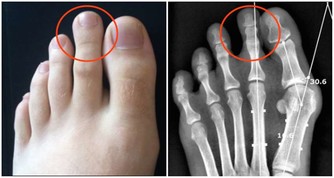

2、怕胖:體重增加,下肢關節承重的壓力也會增加,引起體位、步態變化,改變關節的生物力學,發生膝內翻或膝外翻,也就是常說的“O”形腿或“X”形腿。

3、怕傷:在運動、出行的過程中,如果出現急性外傷,一定要及時去醫院治療,以免留下後遺症。

不及時治療或充分休息,容易留下病根,比如“習慣性崴腳”。

4、怕勤:關節用得太狠,容易導致機械磨損,破壞軟骨。

頻繁爬山、爬樓等是非常傷害關節的。建議大家平時通過慢跑、游泳鍛煉,既不損傷關節又能鍛煉。

5、怕冷:關節受涼會引起疼痛,易導致關節僵硬。